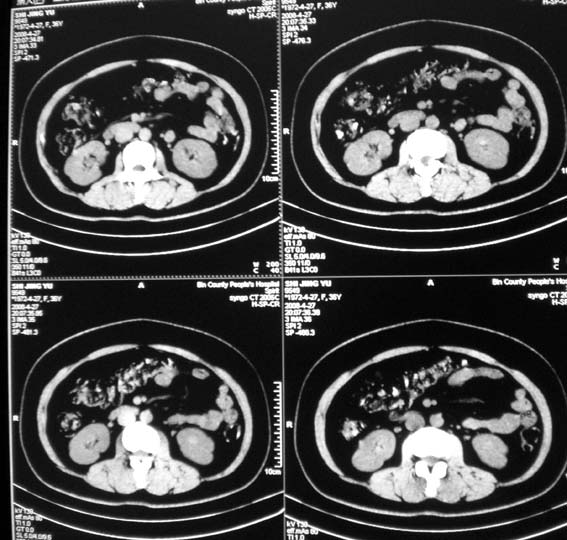

标题: CT13126:腰痛,肾区痛。 [打印本页]

标题: CT13126:腰痛,肾区痛。

女,36岁,腰痛,肾区痛曾有肾囊肿史。

右肾有囊肿,余未件异常

髓质海绵肾?建议mr。